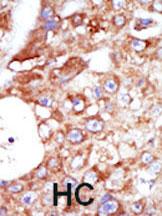

Formalin-fixed and paraffin-embedded human cancer tissue reacted with the primary antibody, which was peroxidase-conjugated to the secondary antibody, followed by AEC staining. This data demonstrates the use of this antibody for immunohistochemistry; clinical relevance has not been evaluated. BC = breast carcinoma; HC = hepatocarcinoma. |